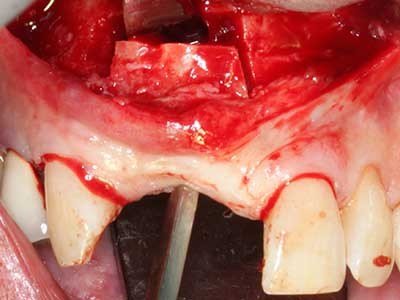

Фиг. 2: Хоризонтален и вертикален латерално-максиларен дефект с висока линия на усмивката с индикация за пре-реконструкция за имплант.

Пиезохирургията има допълнителни предимства при събиране на костни блокове. В допълнение към високата прецизност при остеотомията, описана по-горе, употребата на фините режещи накрайници значително намаляват загубата на материал. Голяма загуба на материал по време на събиране може да се очаква с дебелите накрайници, особено при употреба на борери Линдеман (Lakshmiganthan, Gokulanathan et al. 2012). Базалното разделяне, което е необходимо, особено за присадка на блок при ретромолар, е улеснено от специално създадени правоъгълни триони. В резултат на това, пиезохирургията е разглеждана като прецизна, улеснена и безопасна процедура за събиране на костни блокове в ретромоларното пространство (Happe 2007) (Фиг. 1-12).